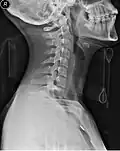

Whenever people have a traumatic head or neck injury, they may have a cervical fracture. This makes them at high risk for spinal cord injury, which could be exacerbated by movement of the person and could lead to paralysis or death. A common scenario for this injury would be a person suspected of having whiplash because of a car accident.[4] In order to prevent further injury, such people may have a collar placed by medical professionals until X-rays can be taken to determine if a cervical spine fracture exists.[5] Medical professionals will often use the NEXUS criteria and/or the Canadian C-spine rules to clear a cervical collar and determine the need for imaging.